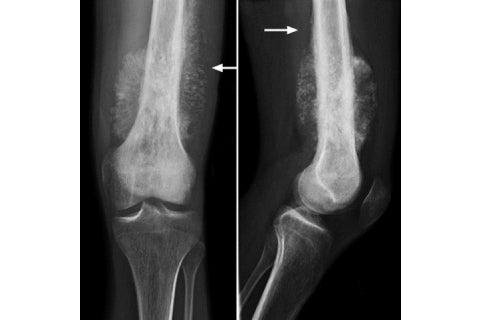

A bone cancer known as osteosarcoma is genetically similar in dogs and human children, according to the results of a study published today by Tufts University and the Translational Genomics Research Institute (TGen), an affiliate of City of Hope. The findings could help break the logjam in the treatment of this deadly disease, which hasn't seen a significant medical breakthrough in nearly three decades.

OS is an aggressive disease and the most commonly-diagnosed primary bone tumor in dogs and children. Though a relatively rare cancer in humans -- with fewer than 1,000 cases each year -- OS strikes more than 25,000 dogs annually.